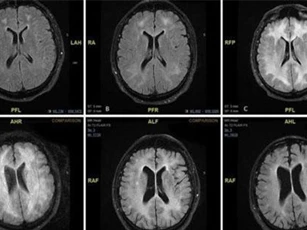

Những bằng chứng quét MRI cho thấy việc lạm dụng cocaine nặng có thể dẫn đến những thay đổi vật lý vĩnh viễn cho não bằng cách "ăn mòn" chất trắng.